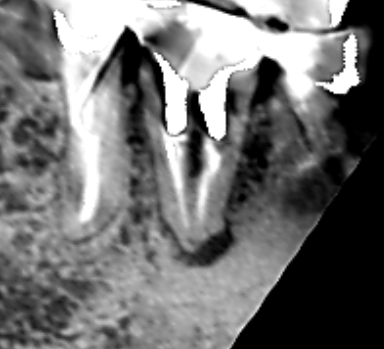

ブリッジの支台になっている上顎側切歯に大きな膿がみられ、この歯を残せなければ無傷の隣の犬歯を削ってブリッジの支台にしなければいけないケースです。できれば、上顎側切歯の膿を治して再度ブリッジの支台として使いたいので、精密再根管治療を行うことになりました。 上顎側切歯の冠状断のCT画像です。 側切歯の根…